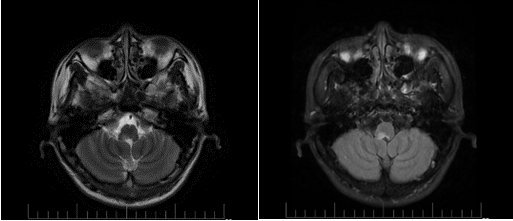

头颅MR平扫+增强:右侧延髓背侧见小片状长T1及长T2信号,弥散像未见信号明显增强,增强后无强化。